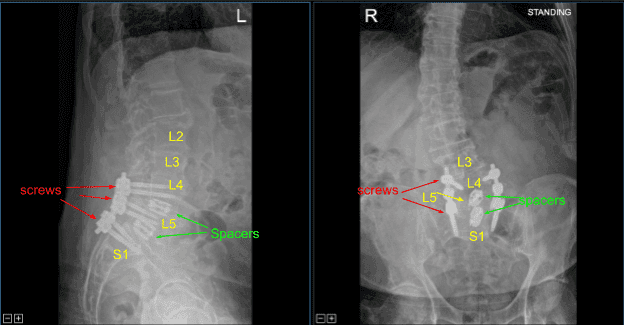

Las varillas de titanio precortadas se perfilaban con curvadores de varilla y se colocaban sobre los tulipanes de tornillo desde L4 hasta S1, y se aseguraban con tapones de bloqueo, todos ellos apretados finalmente con un dispositivo de par y antitorque. Las radiografías AP y laterales finales mostraron una implantación correcta y completa del hardware.

Radiografía postoperatoria